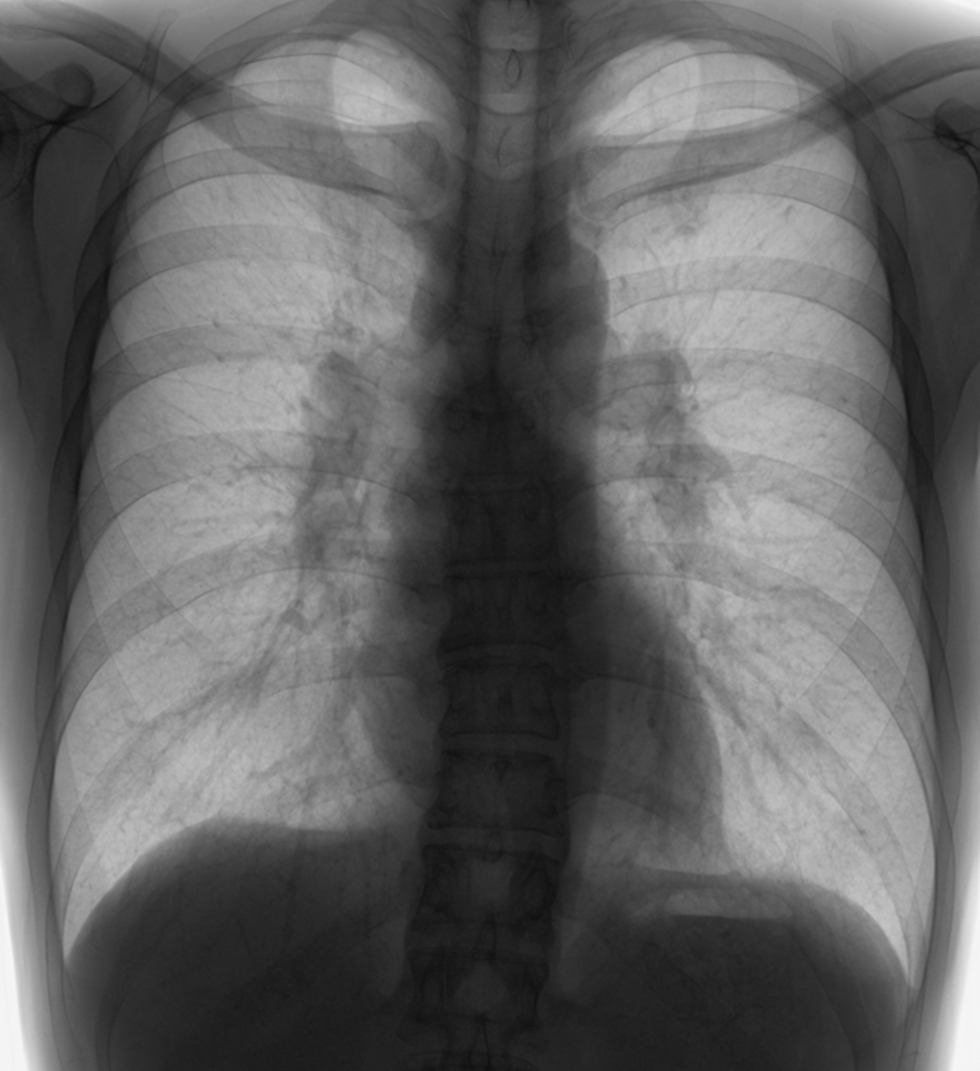

——そして胸部CT——

もろもろ検査→電子タバコの肺障害と診断!